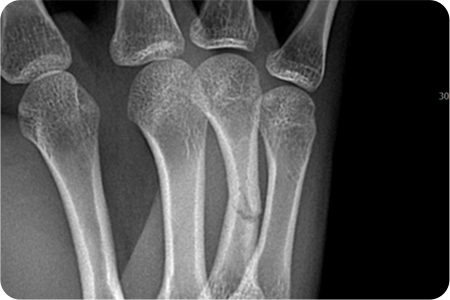

손은 작은 뼈들이 정교하게 연결되어 있어

골절 시 기능 손상이 크기 때문에,

정확한 정복과 고정이 중요합니다.